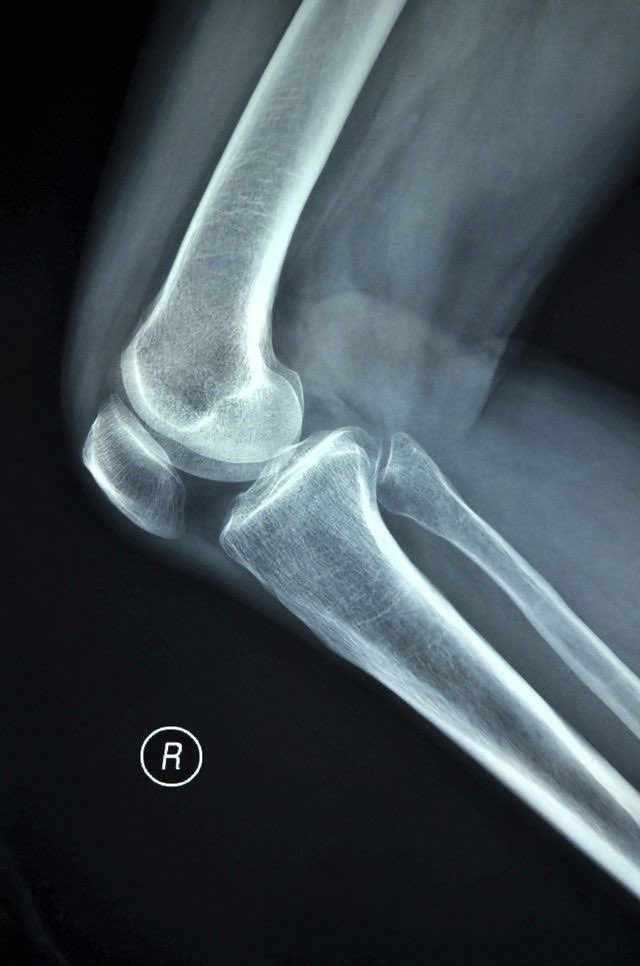

الألم في مفصل الركبة واحمرار وتورم ما حول المفصل.

التصوير الإشعاعي، أو الموجات فوق الصوتية، أو التصوير الطبقي.